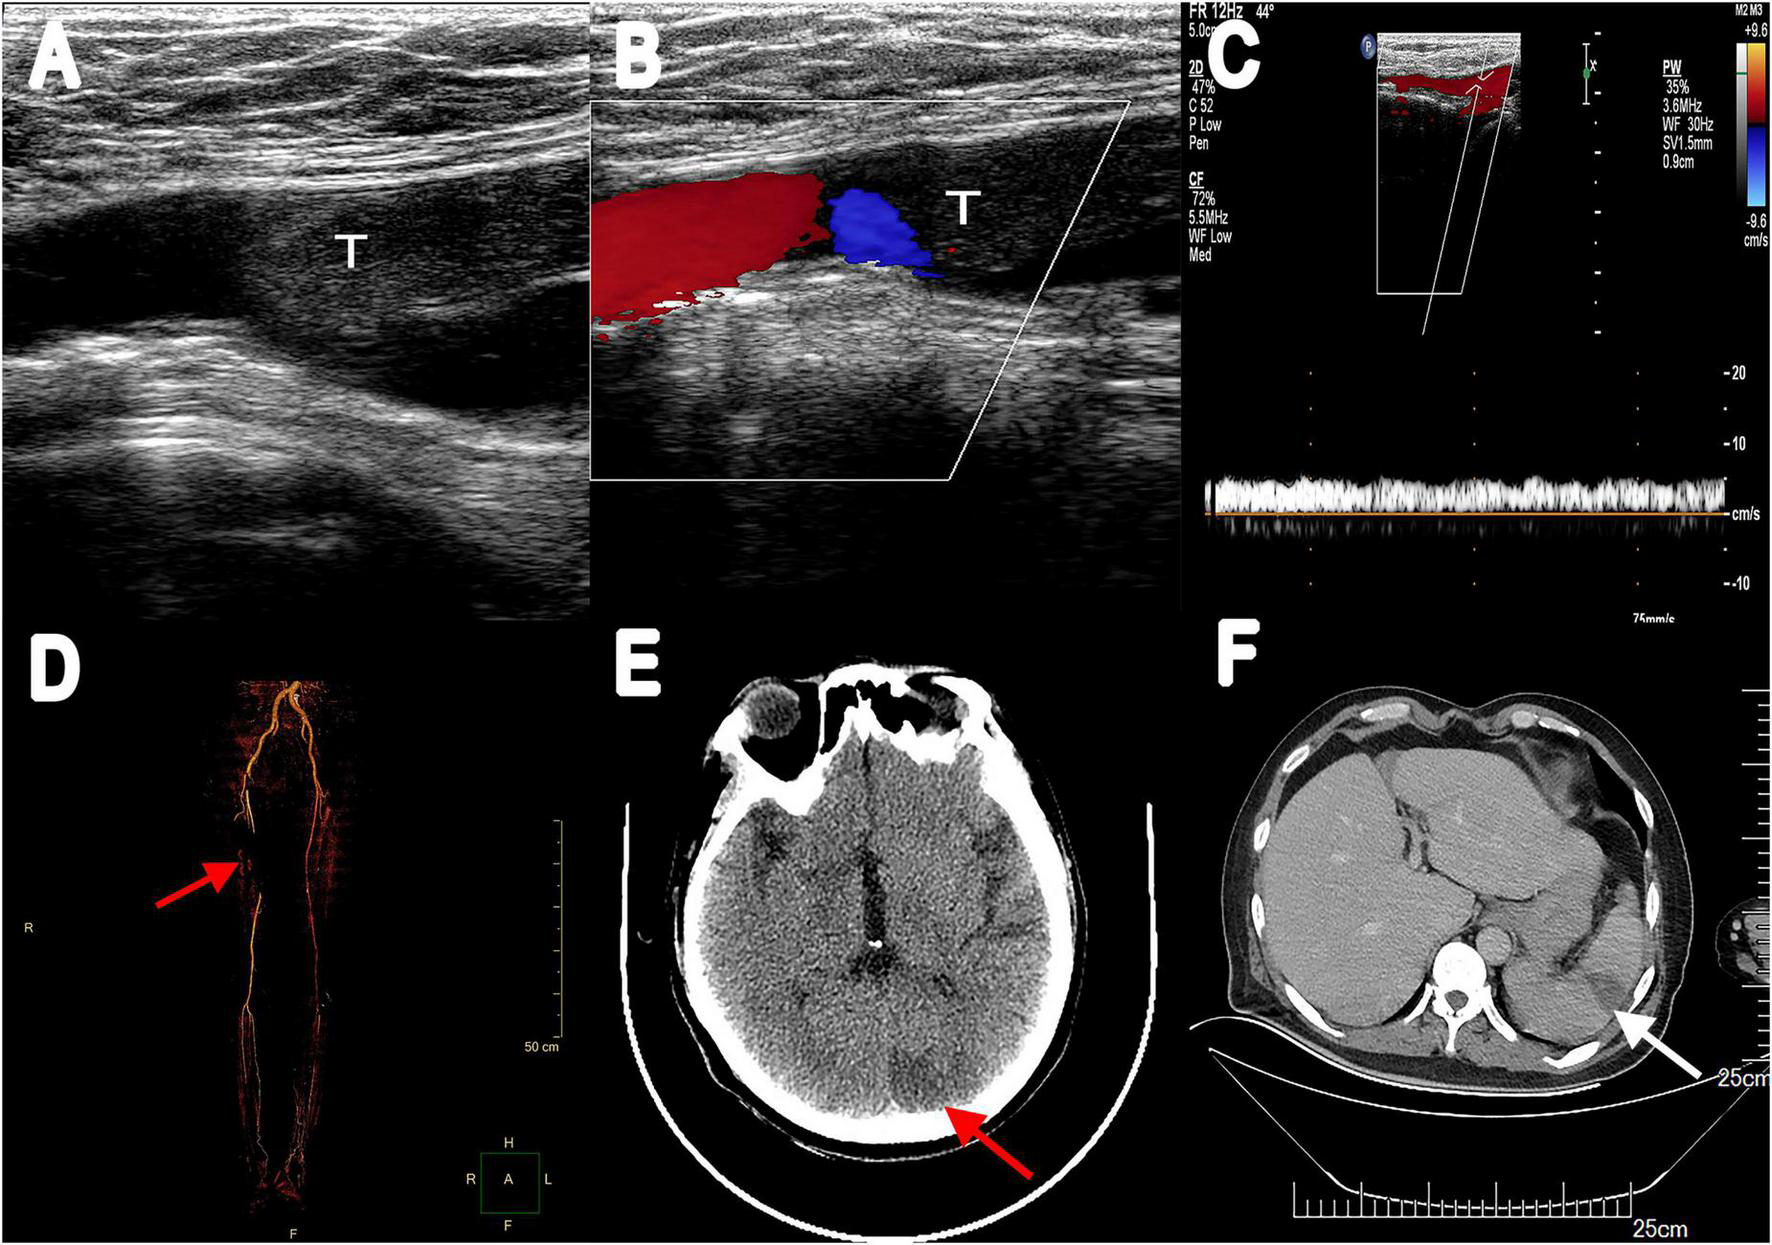

The recommendation for surgery was considered inappropriate as the patient was still in the convalescent phase of Bentall surgery. Antibiotic treatment was continued. On day 21, he suffered from right lower extremity numbness without an apparent cause. The vascular ultrasound showed hypoechoic mass at the distal end of the right common femoral artery with a size of 38 mm × 11 mm without significant activity (Figure 2A), strongly suggesting right common femoral artery embolism, one of the complications of PVE. Color Doppler showed scattered color blood flow signal (Figure 2B) and delayed upstroke waveforms (Figure 2C). The embolism in the right femoral artery was also confirmed by enhanced CT reconstruction (Figure 2D). Our patient immediately underwent arteriotomy to remove the embolism. Macroscopic inspection revealed thrombotic substance and vegetations (Figure 3A). Fiber-like material and red blood cell aggregation were shown under the microscope (Figure 3B). Pathological examination confirmed the right lower extremity artery embolism.

FIGURE 2

(A) Vascular ultrasonography showed hypoechoic filling echo was seen at the distal end of the right common femoral artery. (B) Color Doppler image displayed there was little color blood flow signal. (C) Abnormal spectrum morphology of posterior tibial artery with the significantly reduced blood flow velocity. (D) Multiple filling defects of the right femoral artery were observed in three-dimensional reconstruction (red arrow). (E) Enhanced CT scanning revealed a low-density lesion in the left occipital lobe (red arrow). (F) Abdominal enhancement CT showed wedge-shaped hypodense lesions under the capsule with no enhancement (white arrow). T, thrombus.

On day 28, the patient presented with sudden convulsion. Enhanced CT scanning revealed left occipital cerebral embolism (Figure 2E). Deproteinized calf serum injection (0.8 g once a day) was given to improve brain blood circulation. He underwent a TTE reexamination on day 31, showing that aortic valve and tricuspid valve vegetations were still present while the aortic valve vegetation was smaller compared with the last time (Figure 1C). However, a new mitral valve regurgitation has emerged (Figure 1D). Unfortunately, he presented with decreased muscle tone in the right limb on day 35, and the subsequent CT scan showed another new spot of cerebral embolism.

Furthermore, the patient developed abdominal pain, and the CT scan revealed splenic infarction (Figure 2F) on day 40. After 7 weeks of antibiotic and anticoagulant therapy, The patient’s clinical symptom improved and body temperature was normal (36.5°C). Blood culture was negative. He was discharged after completing 45 days of hospitalization therapy and a follow-up 2 weeks later was advised. Oral warfarin (5 mg/d) was given once daily after discharge to maintain the international normalized ratio between 2 and 3 without significant bleeding tendency. Unfortunately, he died of cerebral infarction on day 55.